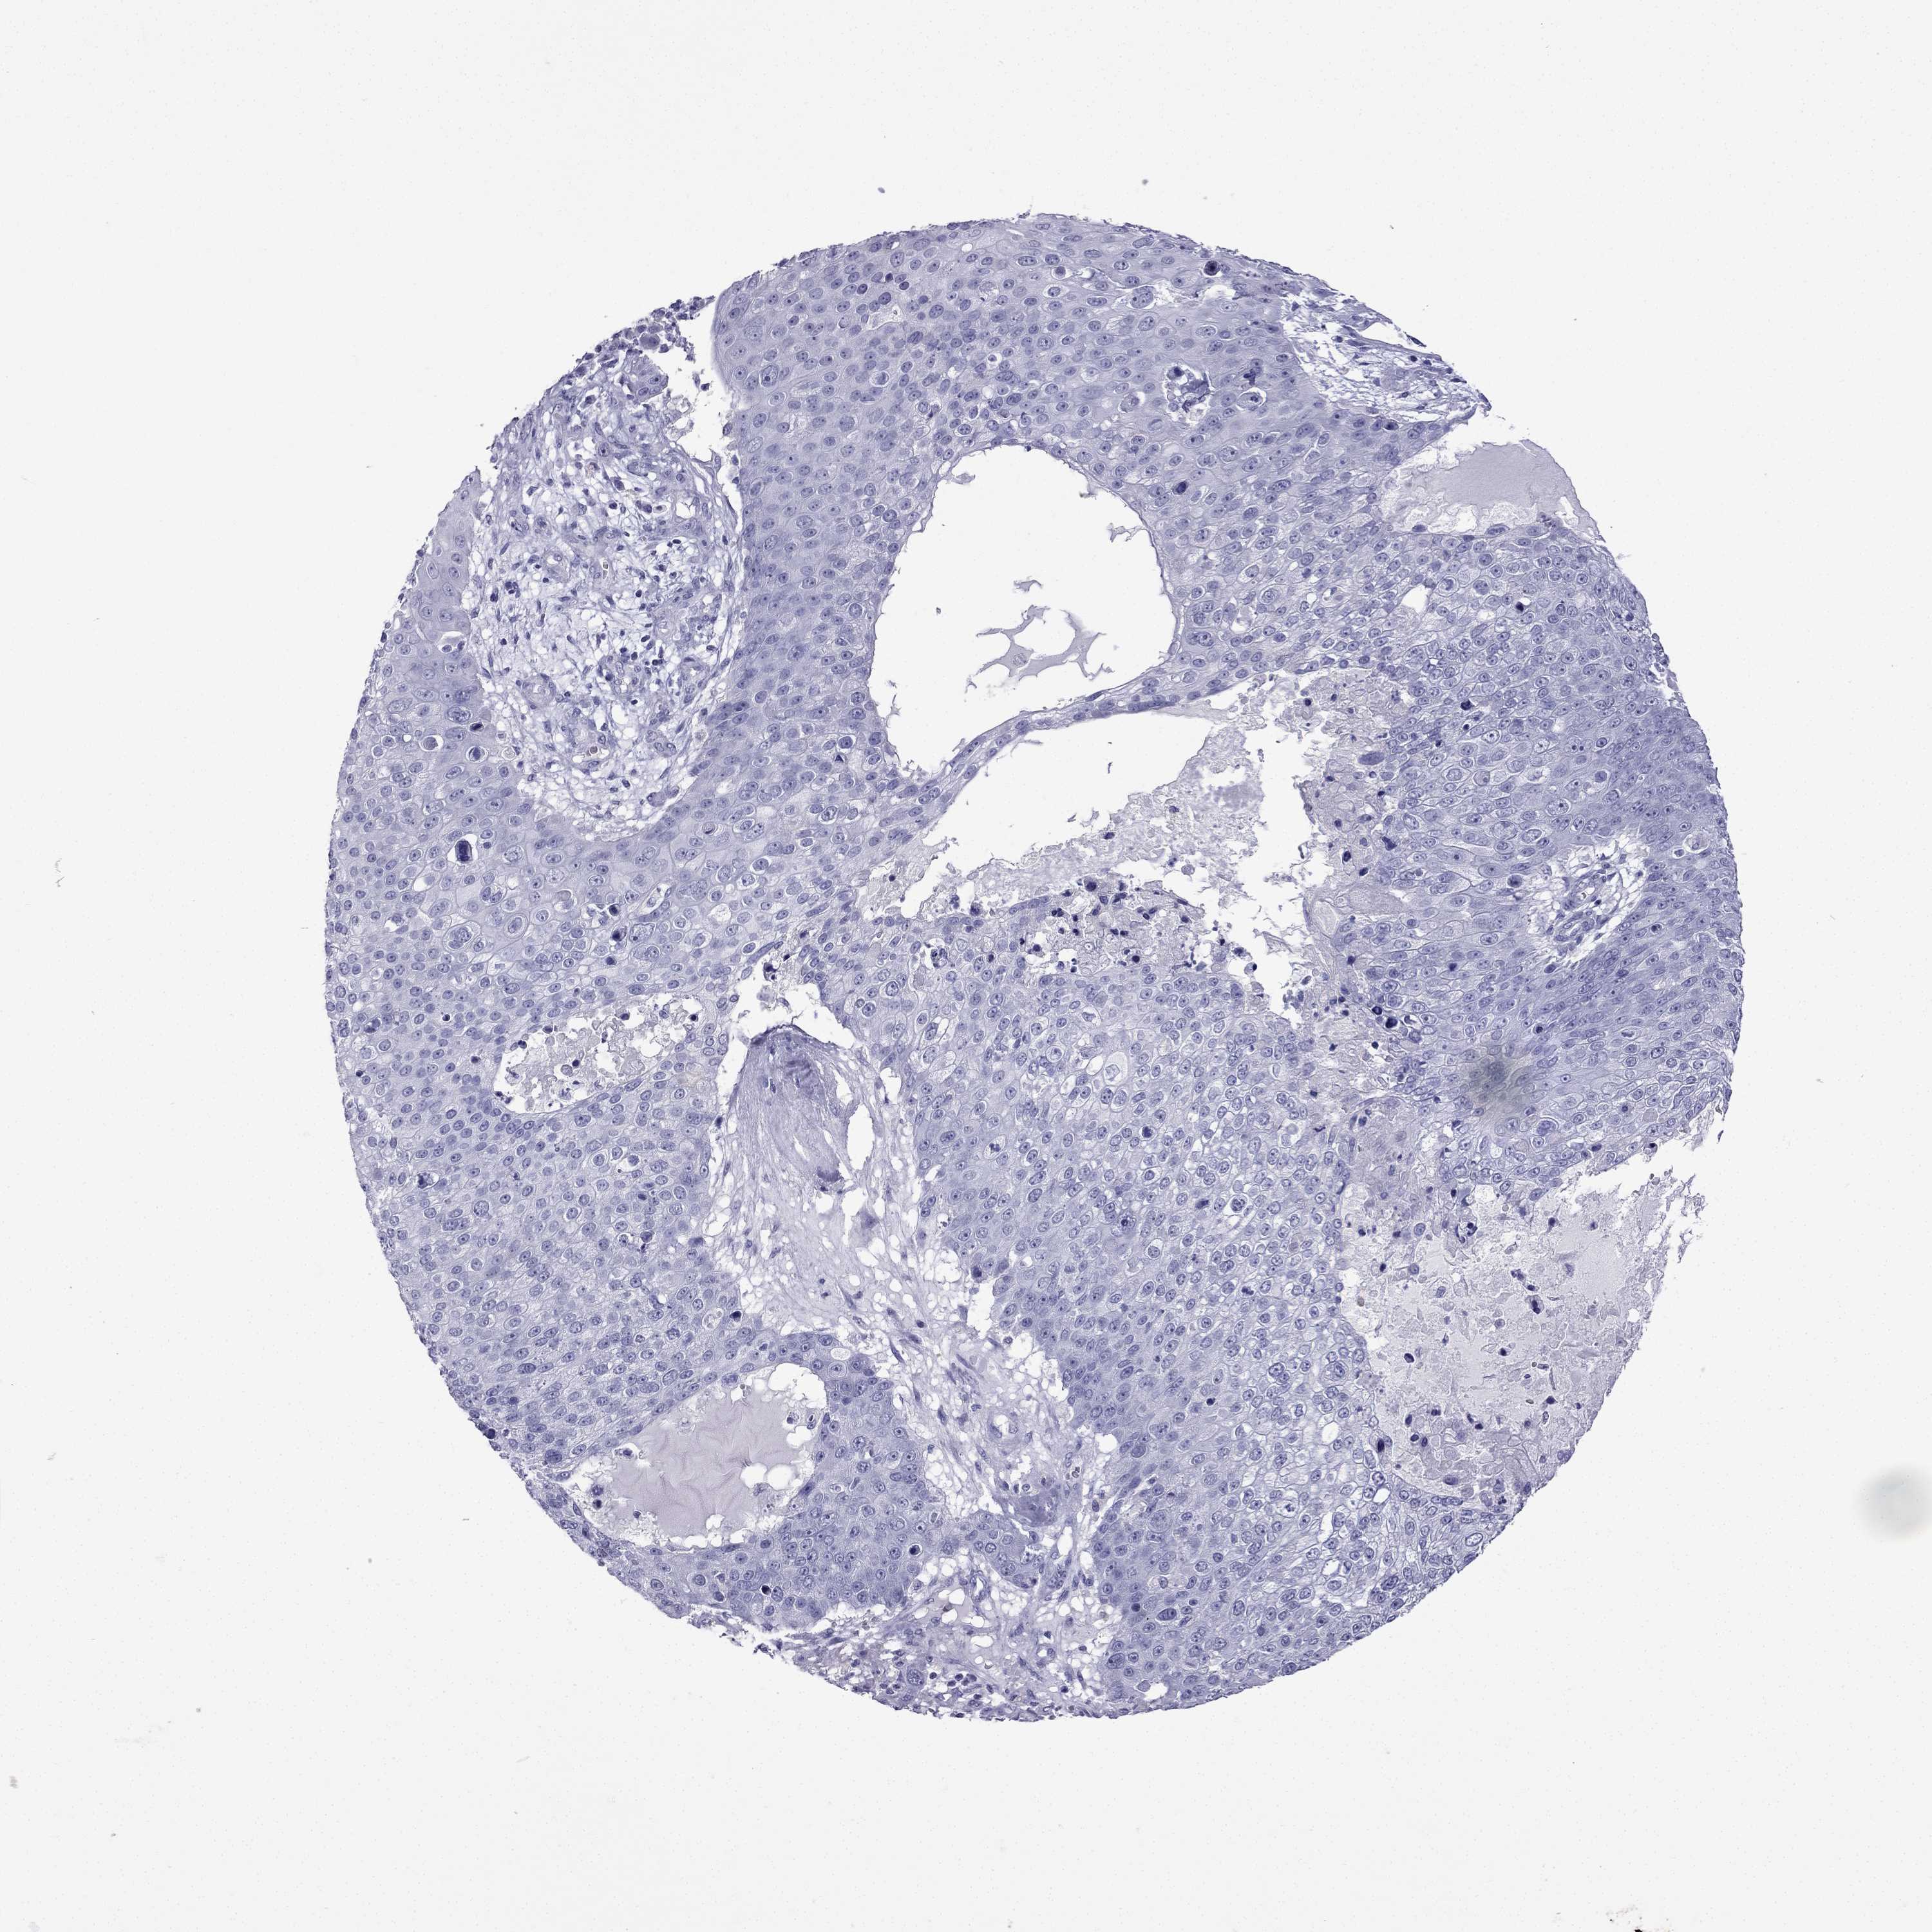

Basal cell and squamous cell cancer

SKIN CANCER - Protein expressioni

A mouse-over function shows sample information and annotation data. Click on an image to view it in a full screen mode. Samples can be filtered based on level of antibody staining by selecting one or several of the following categories: high, medium, low and not detected. The assay and annotation is described here.

Each image is clickable and will lead to virtual microscopy that enables deeper exploration of all samples and also displays staining intensity scores, fraction scores and subcellular localization as well as patient and tissue information for each sample.

Antibody HPA062940

Basal cell carcinoma

Squamous cell carcinoma, NOS